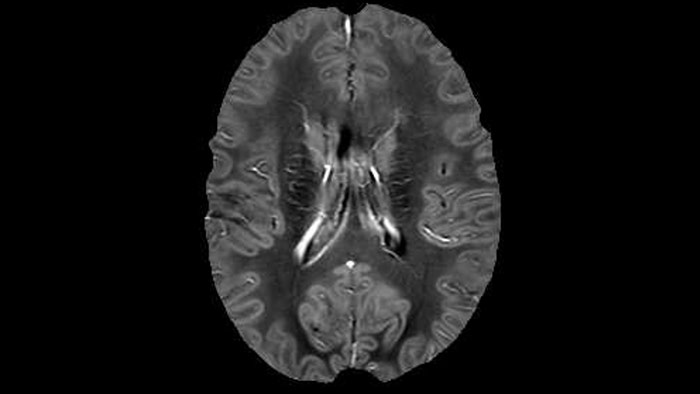

Juxtacortical MS lesion elition

Sagittal 3D FLAIR with 0.3 mm3 voxel volume acquired in 5:12 min. using Compressed SENSE showing a (juxta)cortical MS lesion.